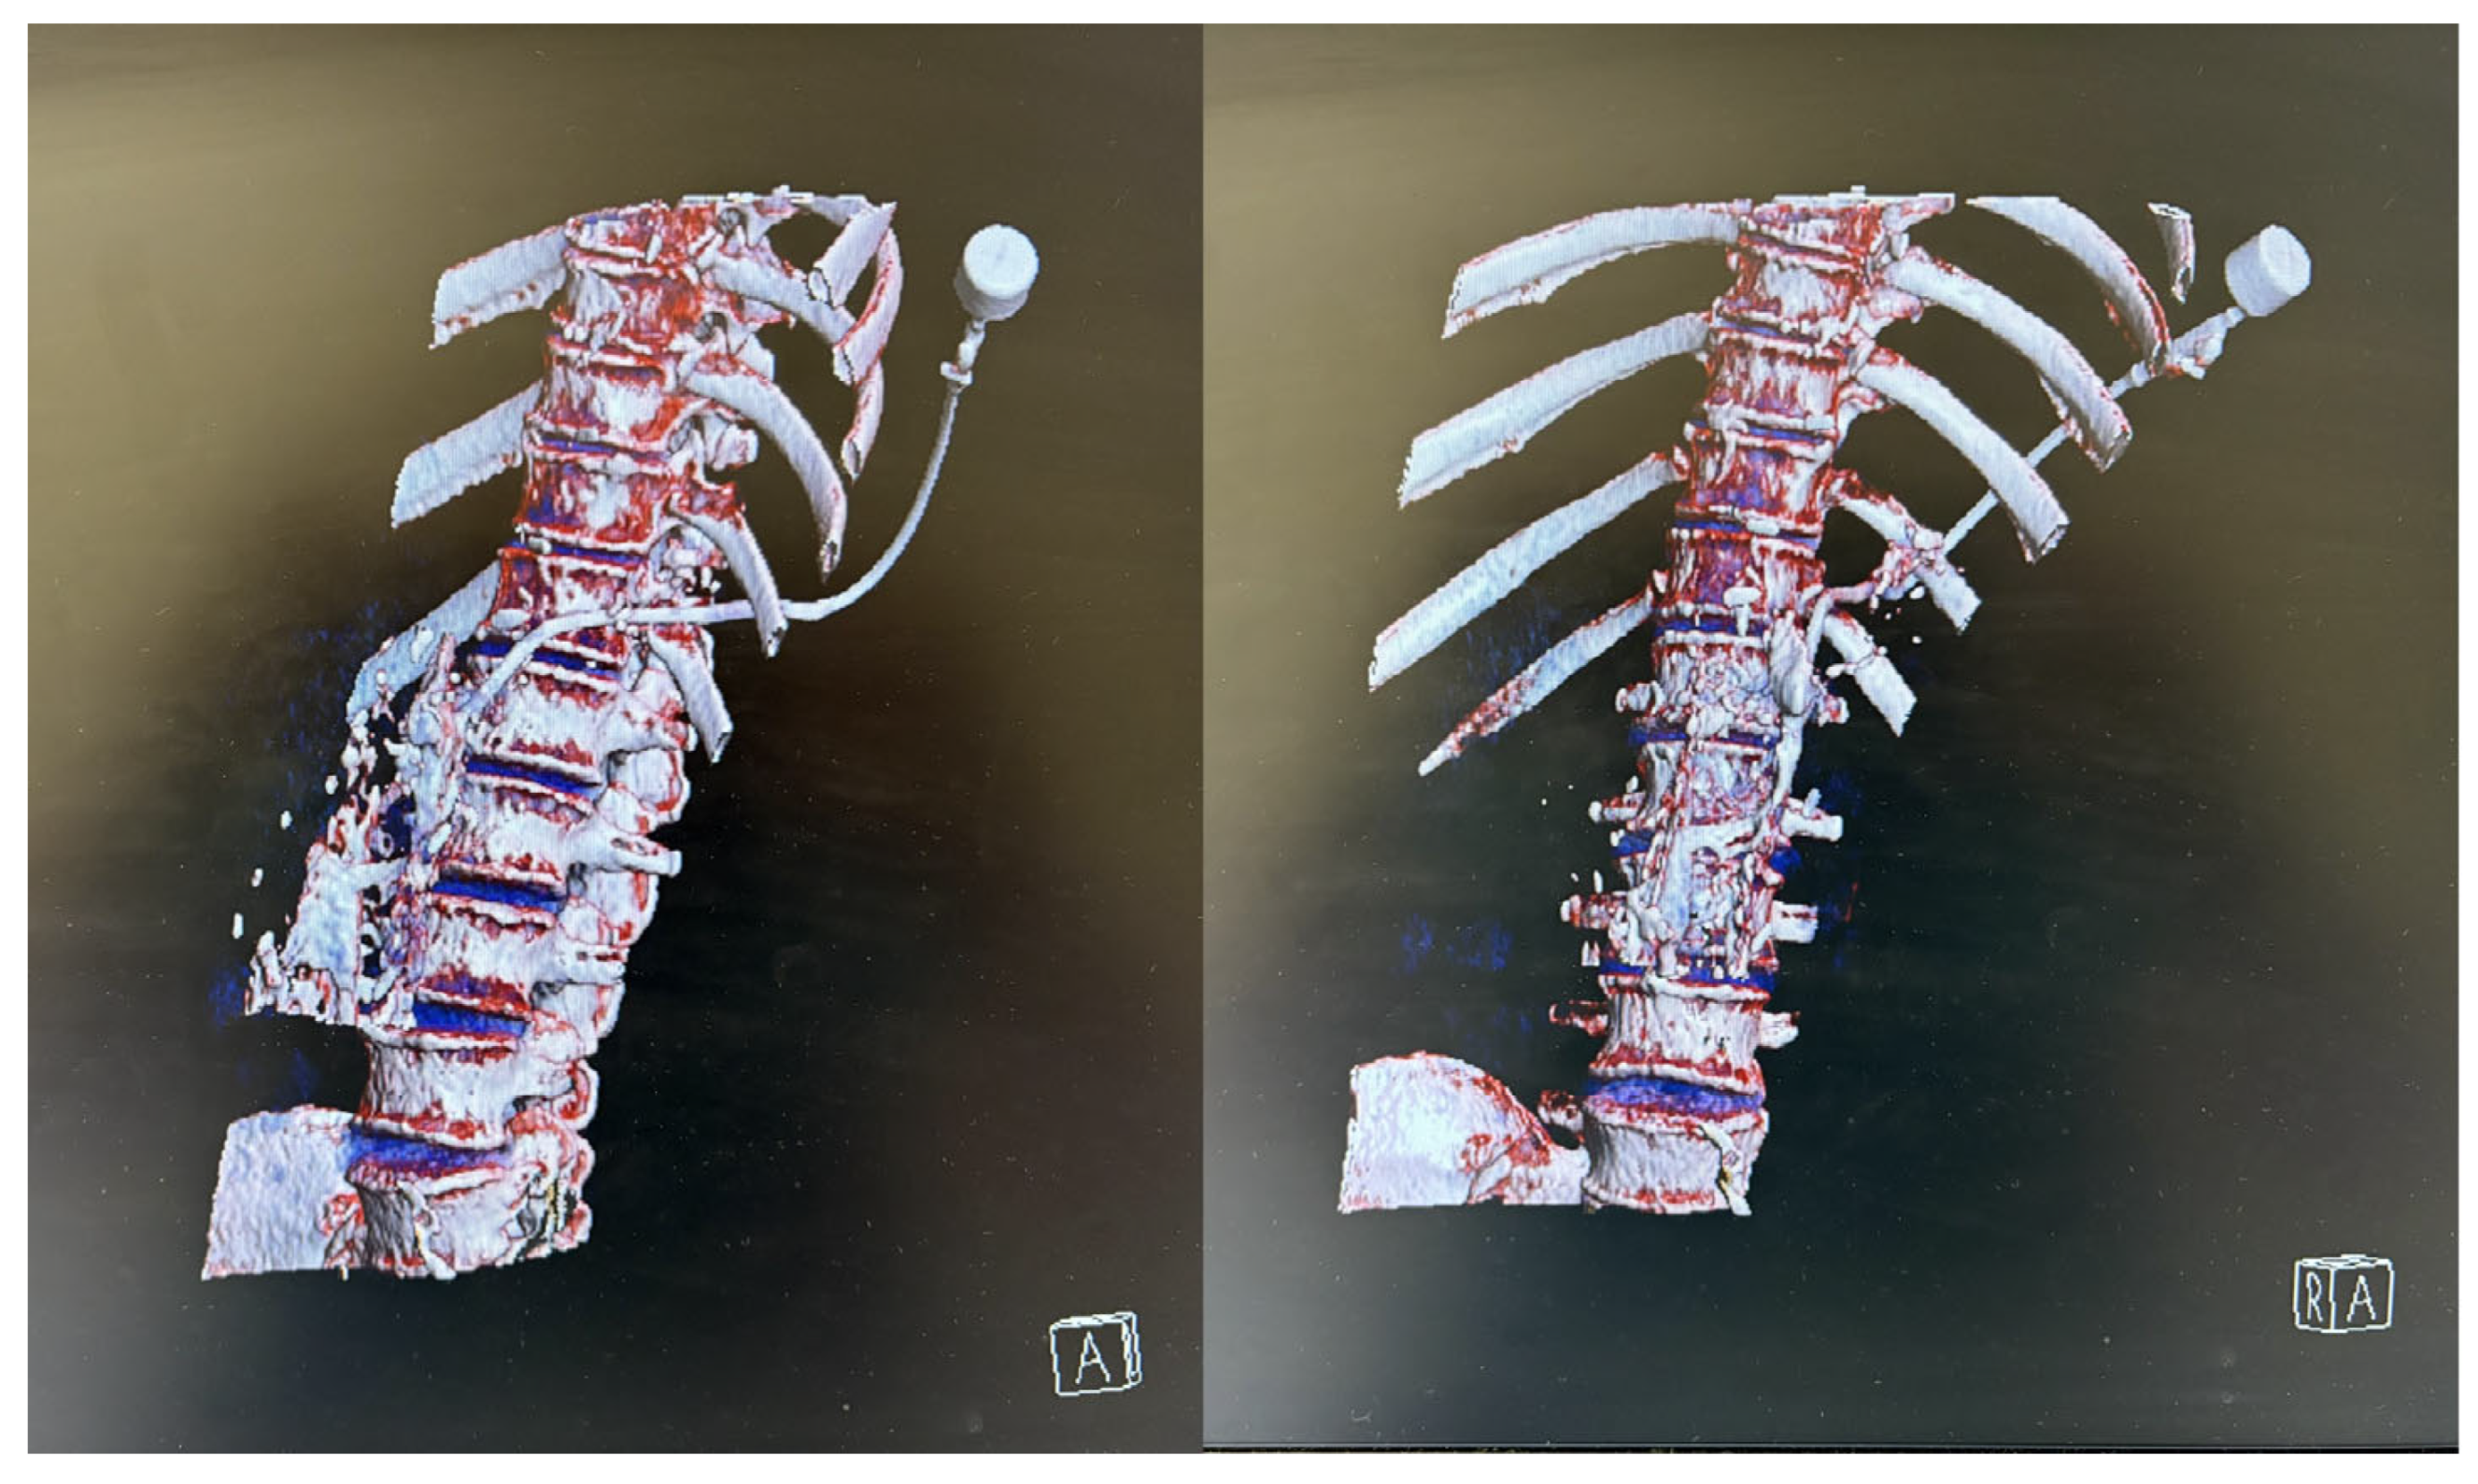

Throughout the procedure, the patient remained sedated, comfortable, and free of unwanted movements, with oxygen saturation between 92 and 96%. The interventional radiologist infiltrated the skin with 2% lidocaine and successfully performed the puncture through the left paravertebral space of the 12th thoracic vertebra. Upon puncturing the AGI, purulent material was aspirated and an 8.5 F drain with an internal locking mechanism was placed (Figure 2). The entire procedure, including preparation, lasted 105 min, with the sedation for the CT-guided percutaneous drainage lasting 65 min. The process was uneventful, with stable vital signs throughout the whole procedure. No adverse events such as hypotension, bradycardia, or respiratory depression were observed.

Figure 2. Three-dimensional image reconstructions of drainage insertion, illustrating the complexity of the procedure and emphasizing the critical importance of patient immobility to ensure accuracy (despite causing discomfort to the patient). Volume Rendering Technique (VRT) on Somatom Definition Flash 256 slices CT Scanner was performed by two experienced interventional radiologists. Image was obtained by syngo.via version 2012B (VA44) imaging software for advanced visualization by Siemens-Halthineers.